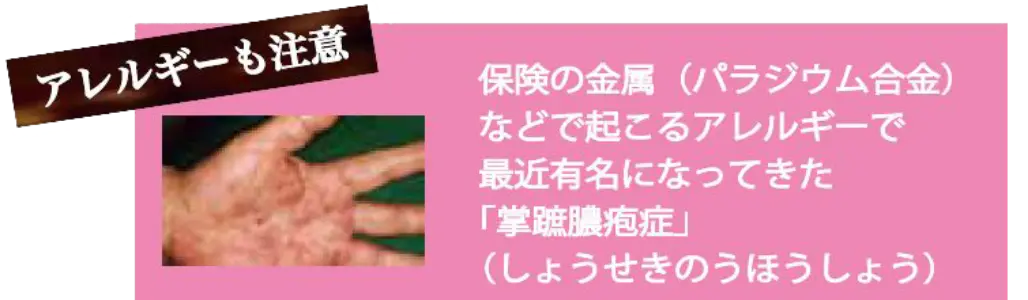

金属が接触して、かぶれやかゆみが出る金属アレルギー。

なかでも銀歯が原因だった、ということはよくあります。

ですが、銀歯が原因と判明しても、アクセサリーのように自由に取り外せません。

原因不明のかぶれやかゆみがある、金属アレルギーの心配がある方も、お気軽にえみは総合歯科へご相談ください。

金属アレルギーを防止できます。

どうして金属アレルギーを予防できるの?

セラミックは金属アレルギーの原因となる成分を含んでいないため、

金属アレルギーの方は、金属の詰め物や被せ物よりもセラミックを選ぶことをお勧めします。